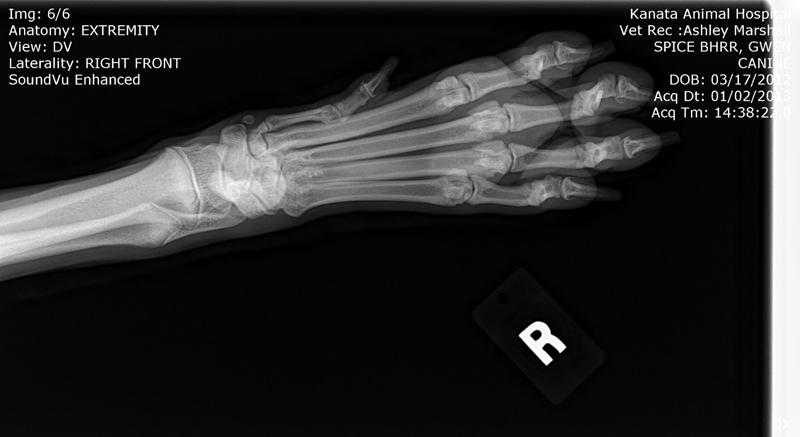

Here are BHRR's Spice's X-Rays: